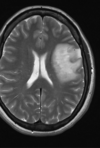

10

Esclerose múltipla